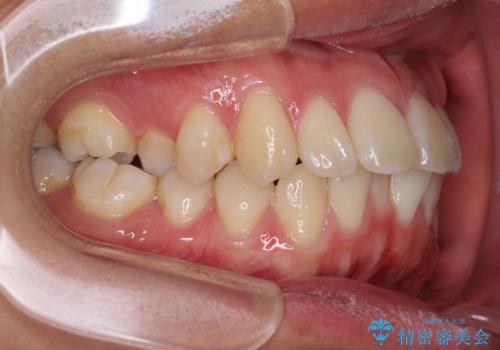

少しでも口元を閉じやすく インビザラインによる前突の解消

- 全体的なデコボコと、前歯の前に出ている感じを気にして来院された患者様です。

患者様と相談の上、非抜歯にてインビザラインを用いて矯正治療を行うこととし、IPR(歯と歯の間)並びに歯列全体の後方移動により口元の突出感の改善することとしました。